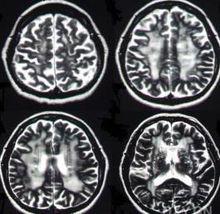

腦萎縮胼胝體變性患者胼胝體密度減低,呈均勻或部分欠均勻的低密度影;無占位性徵象,有腦萎縮表現,其中有廣泛性腦白質病變。胼胝體發生腦梗塞少見,梗塞多為小腔隙性梗塞灶,不會出現與胼低體形態相同的低密度影,腫瘤為占位性病變,有占位徵象。患者的CT表現為胼胝體密度均勻性或部分均勻性減低,CT值均在20HU以下,正常中老年人胼胝體CT值均在23HU以上,具有特徵性,急性期增強可有強化,晚期不強化,診斷不難胼胝體變性,多認為與酒精中毒有關。胼胝體變性臨床表現缺乏特異性,因而診斷困難,以往報導病例多為屍解發現,隨著影像診斷學發展,其早期診斷成為可能。

MRI是診斷胼胝體變性最有價值的診斷方法。MRI與CT比較,有多角度、多序列成像優勢,特別是矢狀位、冠狀位比CT顯示病變更早、更準確、更全面,較易與其它疾病鑑別。FLAIR序列能抑制腦脊液的高信號,使病變顯示更加突出,並可區別病灶的新舊程度,進展期表現為高信號,軟化灶形成後為低信號,還可顯示腦萎縮情況及與胼胝體變性並存的其它部位白質脫髓鞘情況,顯示病灶為高信號,說明病灶為進展期,為臨床治療提供可靠依據。一般認為胼胝體變性異常強化持續不超過20天,發病3周后將不出現強化。有研究提示急性發病的胼胝體變性多累及膝部和壓部,慢性表現的病例體部受累多見。